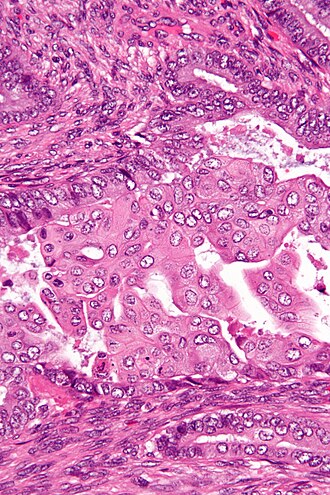

Template:Px Atypical polypoid adenomyoma. H&E stain. | |

| LM | endometrial glands with irregular (non-ovoid) shapes, benign smooth muscle around the glands, morular squamous metaplasia |

| LM DDx | endometrioid endometrial carcinoma, endometrium with squamous morules, endocervical adenocarcinoma |

- Glands with irregular (non-ovoid) shapes.

- Benign smooth muscle around the glands - key feature.

- Morular squamous metaplasia - balls of squamous cells - very common.

- Nuclear atypia (mild).